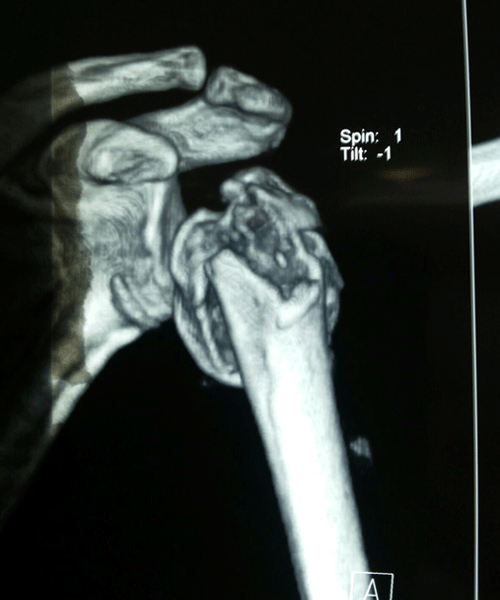

Case:18 Comminuted Fracture Upper Humerus

Female 65 years sustained fall in the house had displaced fracture of head of left Humerus with displaced fragment of greater tuberosity was treated with open deduction and philos plate fixation.

Pre-Op-Xray

Pre-Op CT Scan

CT Scan lateral

Post-Op Xray